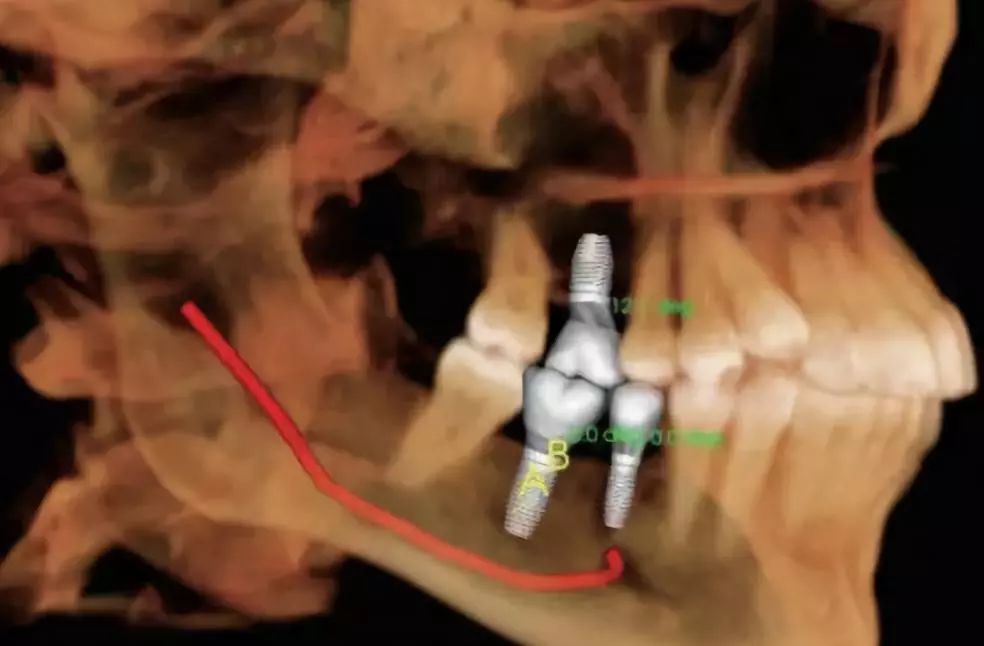

4.神經(jīng)管定位功能

利用口腔CT機(jī)特有的神經(jīng)管著色功能,可以清楚標(biāo)識下頜神經(jīng)管與相鄰的重要解剖結(jié)構(gòu)的相鄰關(guān)系。如下頜阻生智齒拔出時,觀測神經(jīng)管與牙根的距離。